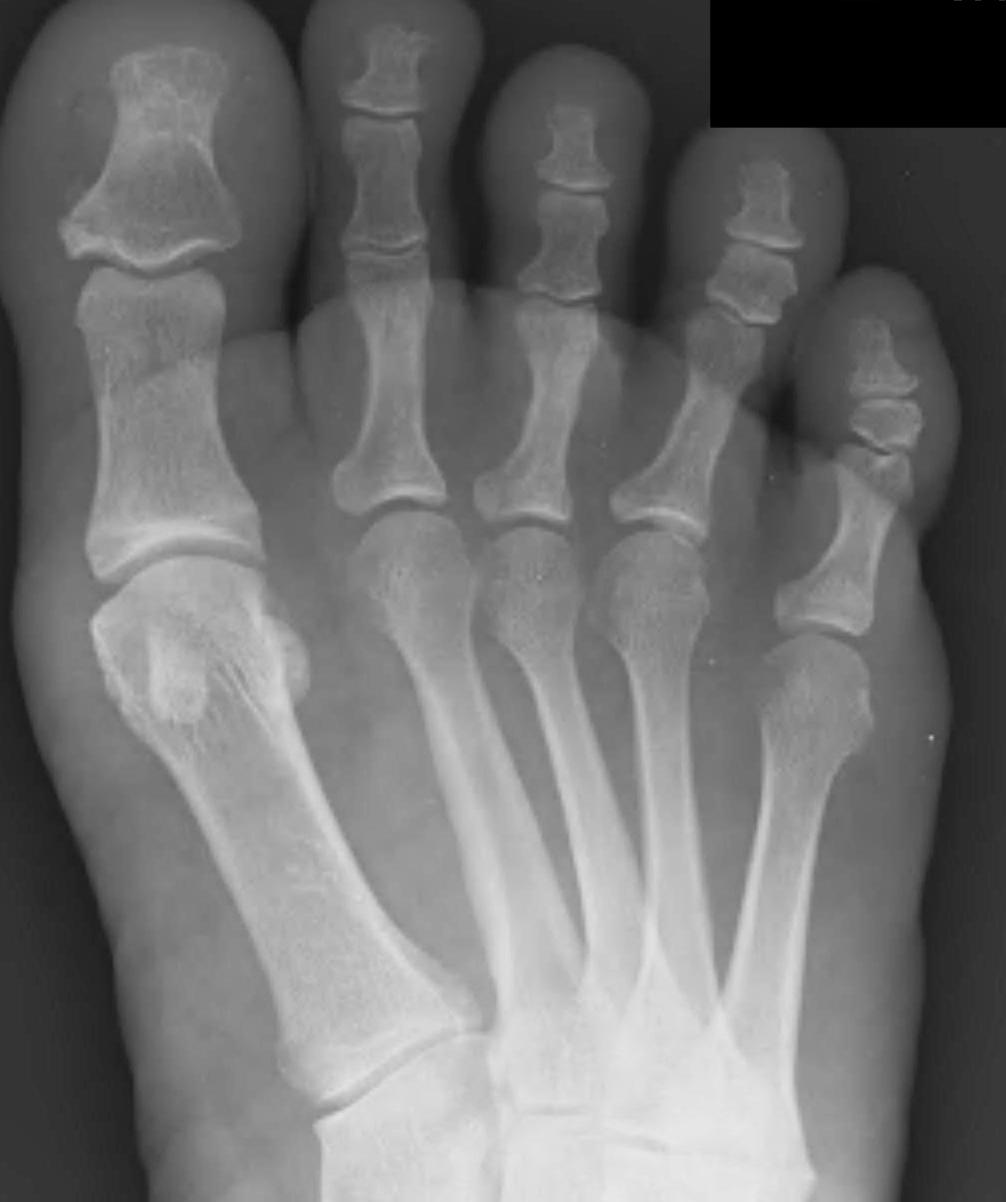

3. Altered forefoot biomechanics / Transfer metatarsalgia

| Hyper-extended MTPJ | Short 1st MT | 1st ray insufficiency syndrome | Iatrogenic |

|---|---|---|---|

| Claw toe / hammer toe | > 2 cm back from 2nd MT |

Splayed forefoot |

Bunion surgery |

| Cavus foot | 1st ray unloaded | 1st ray unloaded | MT head excision |